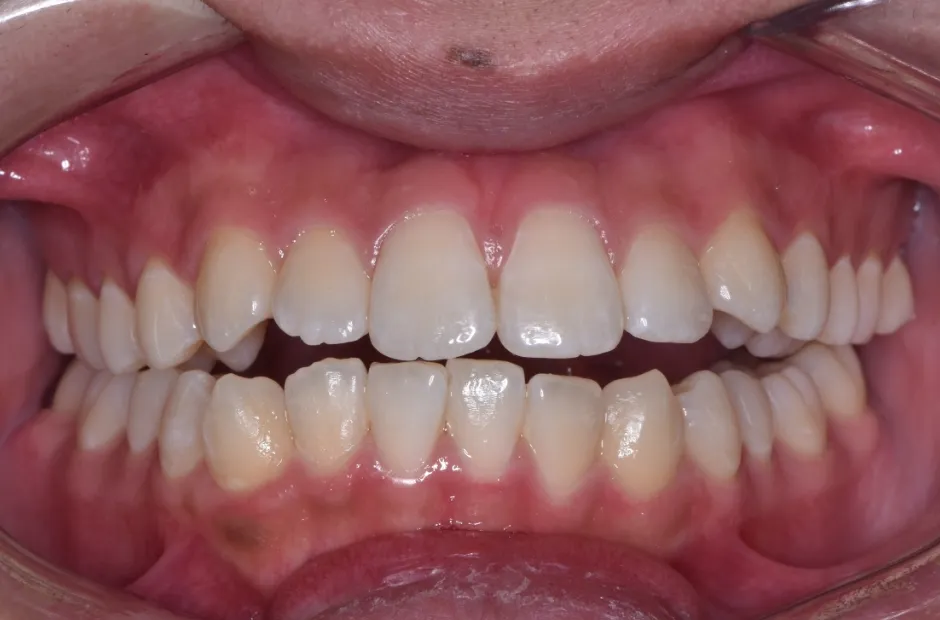

治療前

治療後